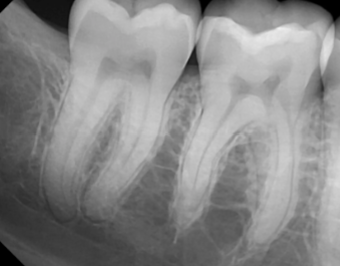

Describe this Radicular Cyst

Epicenter at apex (usually evidence of dental disease or trauma)

Well-defined, corticated

Lucent

Circular

Resorption, Displacement, Expansion (effect on adjacent structures)